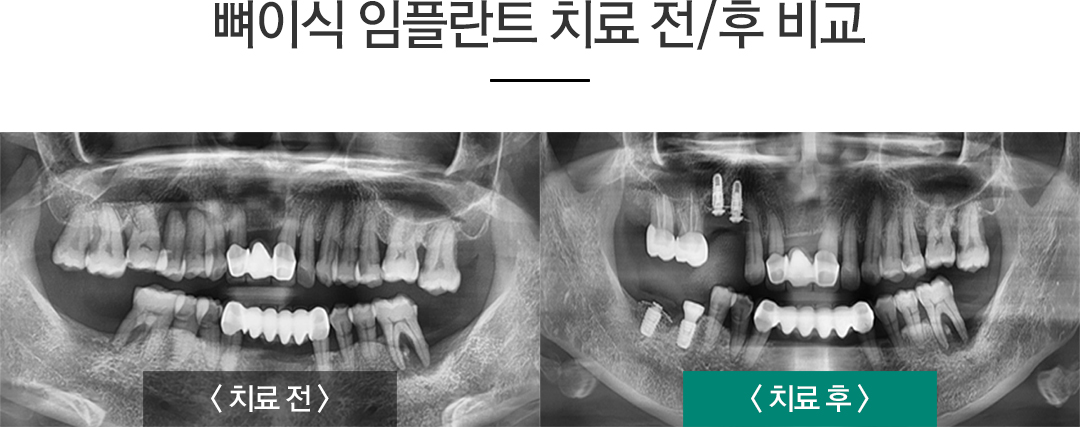

»ÀÀÌ½Ä ÀÓÇöõÆ®